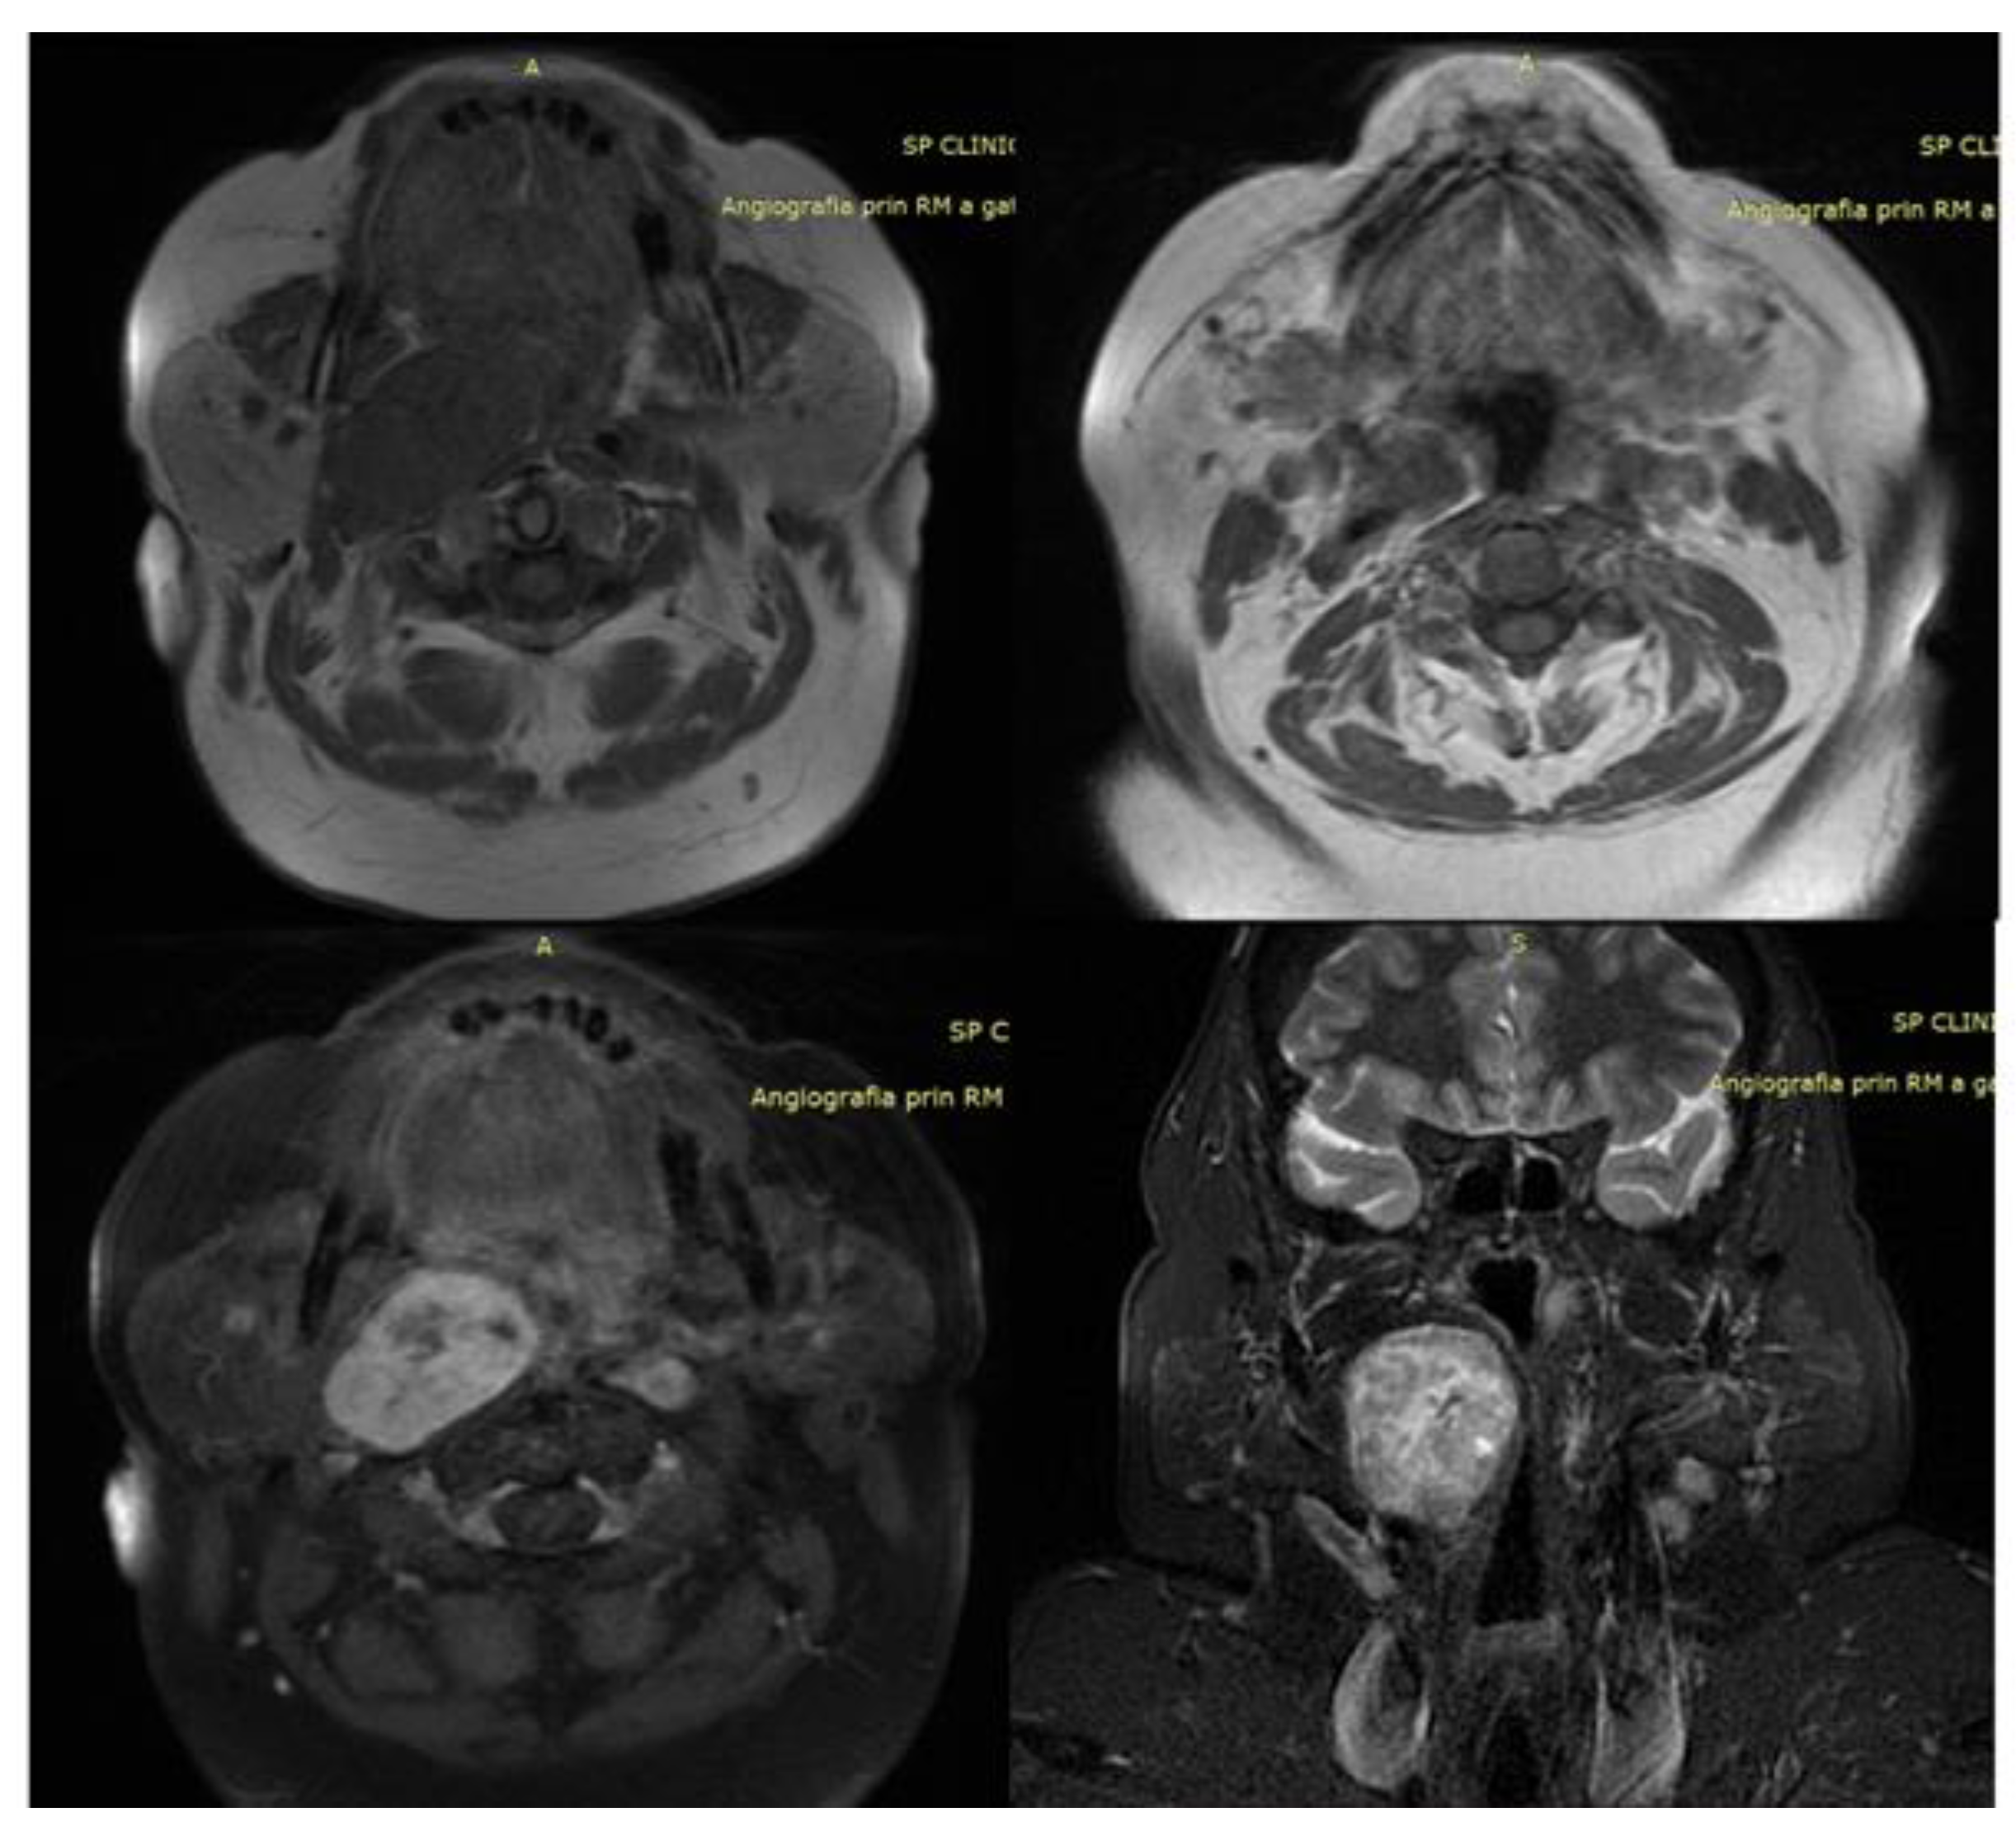

3.5. Computer Tomography, Magnetic Resonance, and Virtual Endoscopy

4.2. Case Scenario 2